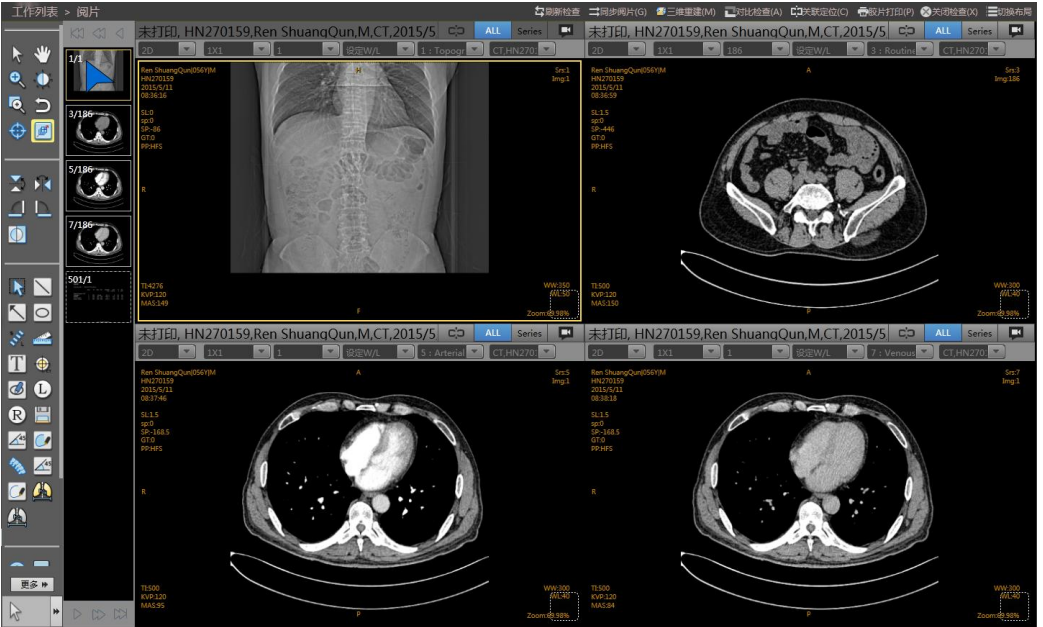

智能医学影像存档与通讯管理云平台[简称:GNPACS管理云平台]V1.0

智能医学影像存档与通讯管理云平台[简称:GNPACS管理云平台]V1.0以病人为中心、服务于临床,利用先进的计算机技术、网络技术和医学影像处理技术结合现代化的医院管理模式,以全院影像信息平台建设内容为主结合患者数据长期可靠存储与科学有效管理。进一步完善医院的信息化建设,从而提高诊疗效率,以及更大范围的实现医疗信息共享。

济南国宁信息工程有限公司专注医疗信息化领域,为数据安全、管理、挖掘提供卓越的产品、服务及全方位的解决方案,推出了针对用户核心数据的系列产品:智能云平台健康体检平台、医院信息化管理(HIS)平台、医院检验(LIS)平台、医院影像管理(PACS)平台、排队叫号平台等。